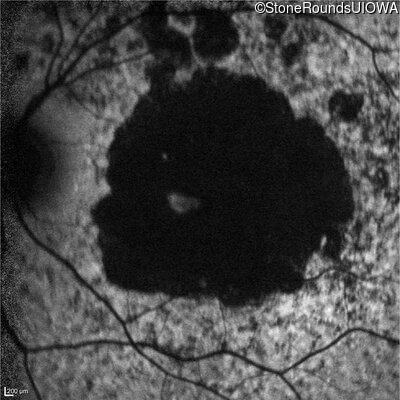

Age at visit: 30 years

This 30 year old man first noticed poor vision in dim light when he was five years old. His visual acuity began to fall in his early 20's.